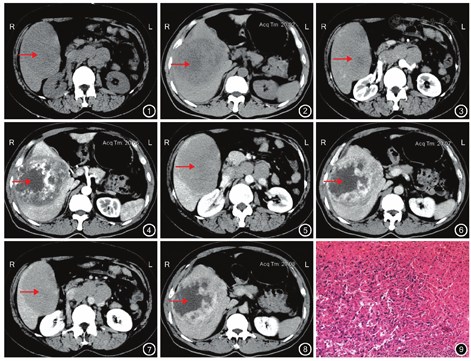

9例患者肿瘤均呈低密度影,CT值为32~46 HU,平均CT值为41 HU,其中密度均匀3例(图1),密度不均匀6例(图2);肿瘤界限清晰6例,界限不清晰3例;肿瘤坏死囊变4例,肿瘤中心有条片状稍高密度影4例,瘤内见小片状钙化1例。

动脉期:9例患者肿瘤均呈轻、中度不均匀强化,CT值为63~76 HU,平均CT值为68 HU,其中3例肿瘤周边呈小片状或结节状强化(图3),6例肿瘤中心呈斑片状或絮状强化(图4)。4例肿瘤中度强化,密度高于正常肝实质;5例肿瘤轻度强化,密度等于和略低于肝实质。

门静脉期:9例患者肿瘤均呈轻、中度持续渐进性强化,密度不均匀,CT值为56~71 HU,平均CT值为63 HU,其中3例肿瘤强化范围扩大,有融合充填趋势(图5);6例肿瘤中心及周边小片状或结节状强化和网格样强化,并向中心充填(图6)。2例肿瘤中度强化,密度高于正常肝实质;7例肿瘤轻度强化,密度等于和略低于肝实质。

延迟期:9例患者均见肿瘤内强化缓慢退出,CT值为50~60 HU,平均CT值为53 HU,其中3例肿瘤周边强化结节密度降低(图7);6例肿瘤强化部分融合并向中心充填,坏死部分无强化(图8)。2例肿瘤密度略高于正常肝实质;1例肿瘤密度等于肝实质;6例肿瘤密度略低于肝实质。

病理学检查:肿瘤切面呈灰黄、灰褐色,部分区域呈鱼肉状,内部均见出血、坏死。镜下见瘤细胞呈弥漫性增生,肿瘤组织由不规则、相互吻合的血管腔隙组成,沿肝窦间隙浸润性生长;瘤细胞呈梭形、圆形或不规则形;细胞质轻度嗜酸性,细胞核染色质深,长形或不规则形,核仁大小不等。见图9。